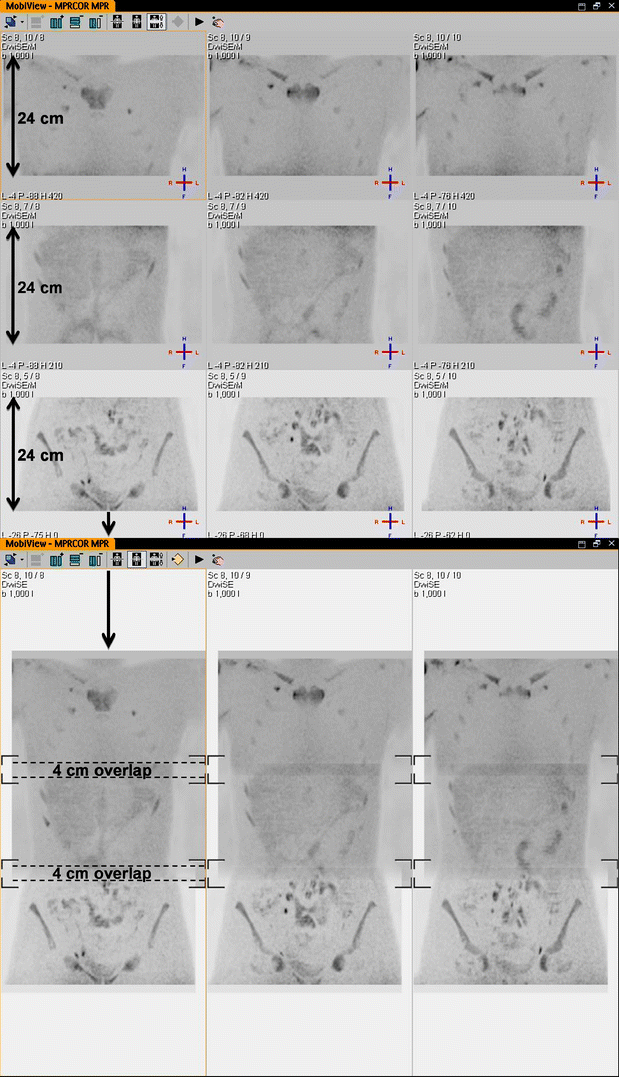

Fig. 7

Separately imaged stations can be merged with sophisticated software, creating the whole-body image